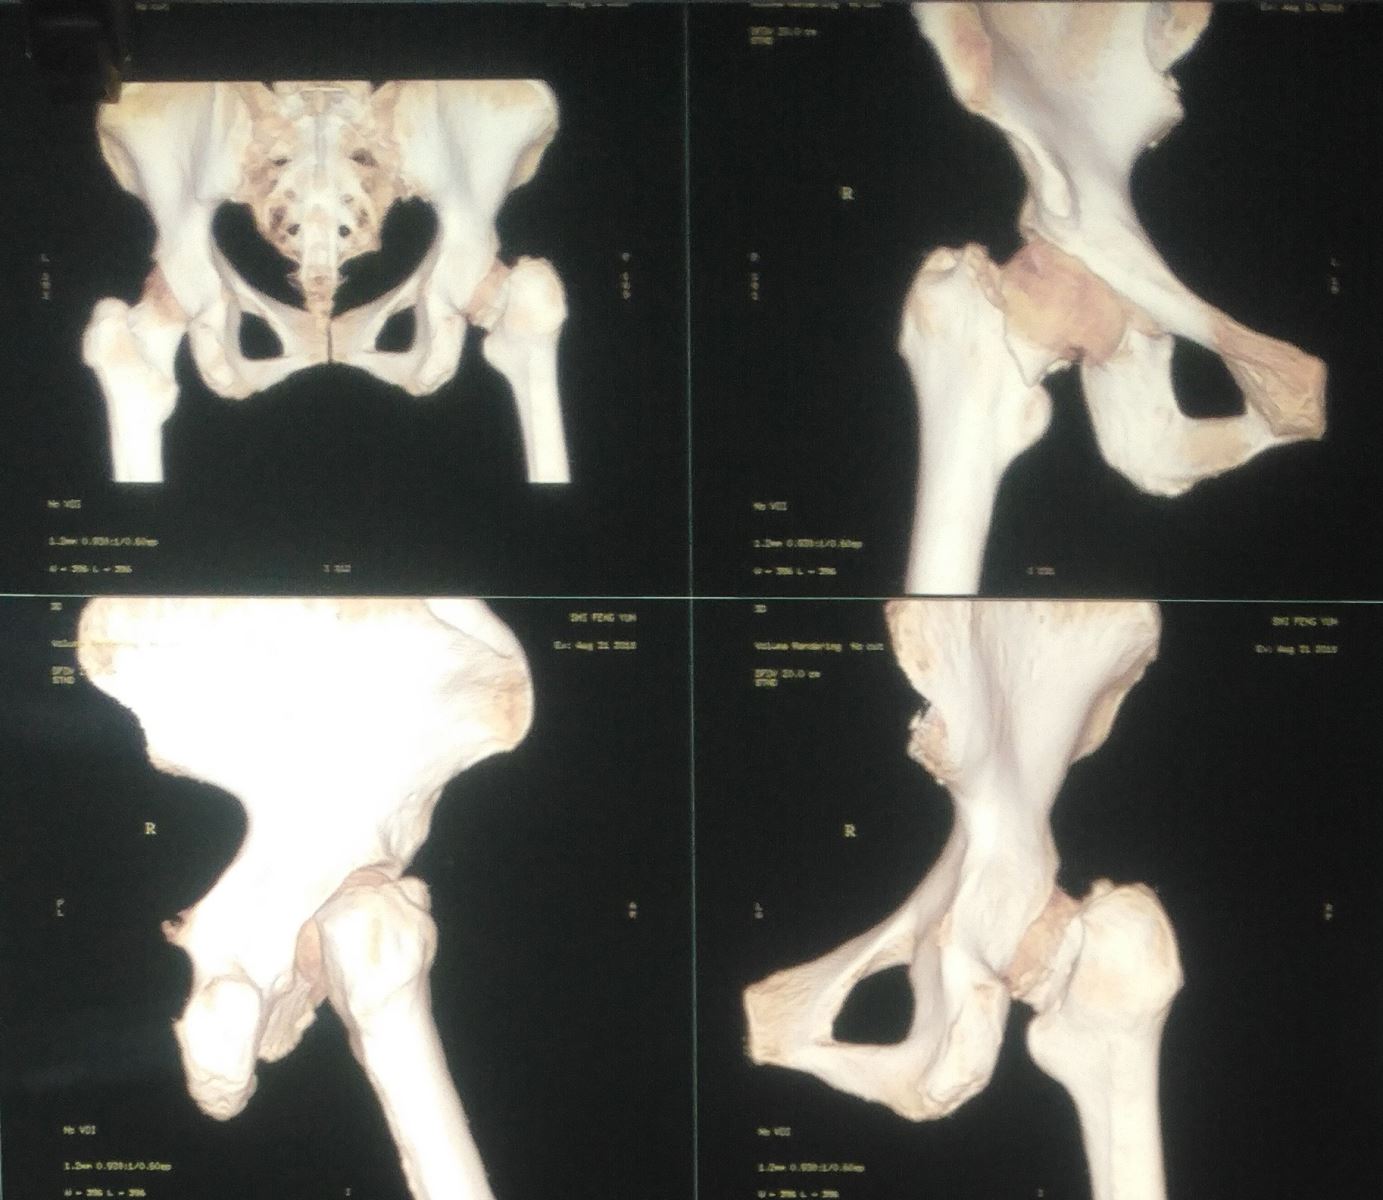

2018年金秋伊始,年近70岁史阿姨,清晨像往常一样到广场锻炼身体,并且要为马上进行的广场舞决赛做准备工作,但一次不小心的摔倒却让她错过了比赛,家人立即带老人到我院检查,却得知:这并不是简单的皮外伤,X线片清晰的显示史阿姨的右侧股骨颈骨折。我院骨一科接诊医生立即为患者办理了住院手续及术前检查,并拟定了手术方案,因史阿姨的右侧股骨颈骨折属于头下型骨折,Garden IV 型属于不稳的型骨折,如果选择固定,术后股骨头缺血性坏死的几率较高,且术后不能早期负重,建议行人工全髋关节置换术,迅速与麻醉科、心内科多学科联合评估手术风险,排除了其他手术禁忌后,于伤后48h内就为史阿姨做了手术,术中应用小切口、保护梨状肌、控制出血、修复外旋肌群及关节囊及不放置引流管等方法,术后指导踝泵练习、应用抗凝药物等为快速康复奠定了基础。并在术后24h帮助史阿姨重新站起负重,术后48h就可以在助行器辅助下行走,术后第四天就办理了出院。出院前除了告知常规的术后注意事项,另外提醒史阿姨别忘了广场舞的动作,因为3个月后又可以在广场展现风采了,看到史阿姨喜笑颜开的表情,无疑给了我们医护人员最大的欣慰。